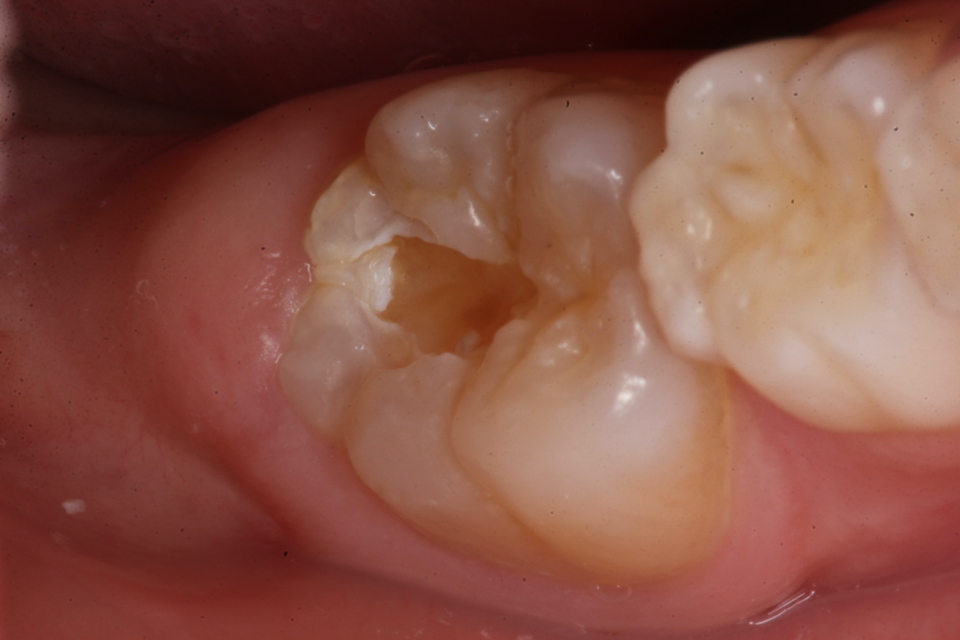

若い子の歯科治療シリーズ1.8(頬側面カリ… 2025.09.20